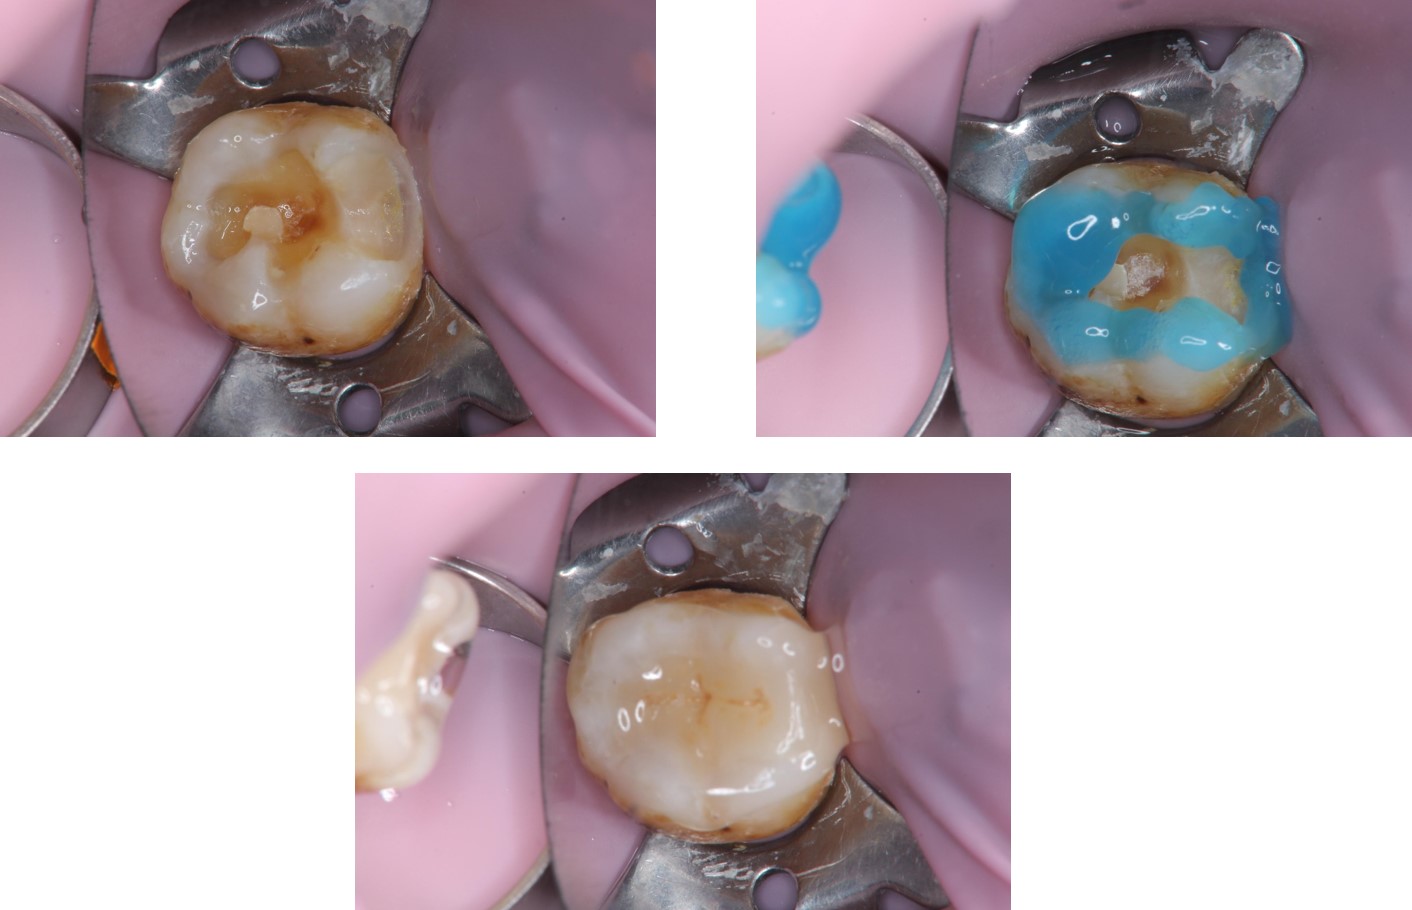

治療前,右下顎第二大臼齒二次蛀牙

右下顎第二大臼齒二次蛀牙

上橡皮障黏著